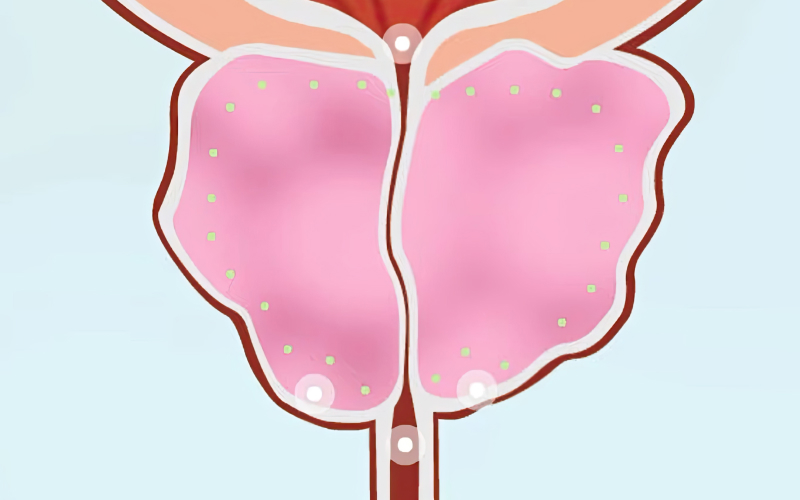

절제 부위를 정확히 지정합니다.

It’s Advanced! 로봇 워터젯 수술,

골드만 로봇 워터젯 수술은 통증·재발·부작용 부담을 최소화해 안전하고 만족스러운 치료를 제공합니다.

로봇 워터젯 수술(아쿠아블레이션)은 수술 시간이 7~15분으로 짧아 부담이 적습니다. 수술 당일 퇴원이 가능하며 많은 환자들이 치료 결과에 만족하고 있습니다.